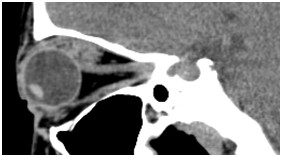

眼眶(病例-眼上静脉扩张)